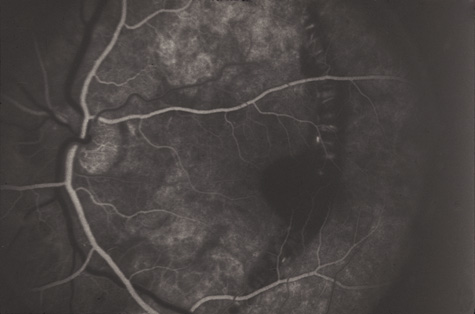

Commotio retinae (Latin, meaning retinal contusion) is a contrecoup injury. It can occur peripherally (Fig. 8) or centrally, in which case it is called Berlin's edema (Fig. 9). Immediately and for several hours after the trauma, the retina appears normal, although the patient may complain of decreased vision. Thereafter, the outer layers of affected retina become opaque. On fluorescein angiography, the opaque retina blocks background choroidal fluorescence, and in most cases there is no leakage into or under the retina (Fig. 10). For years, clinicians had difficulty explaining this blockage, because leakage is expected in conditions with edema. It was then shown in experimental animals and in human autopsy eyes that Berlin's edema is not true edema. The retinal opaqueness is the result of intracellular edema and fragmentation of the photoreceptor outer segments and intracellular edema of the underlying pigment epithelium. There is little or no intercellular fluid.66–69

Fig. 10. A: Commotio retinae in the macula. B: On the angiogram there is no leakage in the area of commotio retinae.

The visual acuity in commotio retinae varies from 20/20 to 20/400 and does not always correlate with the degree of retinal opacification. There is no known treatment. The prognosis is usually excellent except in cases with associated subfoveolar choroidal rupture and in cases with choroidal rupture with subfoveolar hemorrhage. Poor visual recovery can also be expected in cases with severe retinal pigment epithelial damage. Serous retinal detachment (Fig. 11) signals this condition, which can be confirmed by leakage of fluorescein into the subretinal space.70